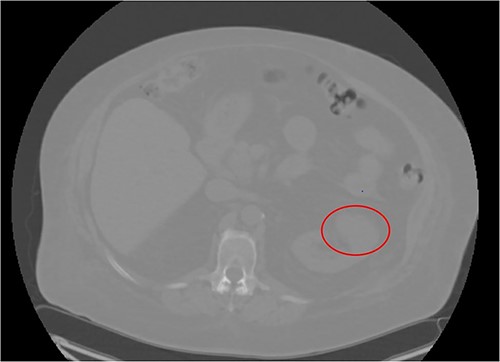

A 66-year-old morbidly obese female with relevant past medical history of type 2 diabetes mellitus, hypertension, and end stage renal disease on peritoneal dialysis (PD) was found to have an incidental enhancing right renal mass concerning for neoplasm on computerized tomography (CT) urogram workup for bacterial peritonitis secondary to streptococcus agalactiae bacteremia (Figs 1 and 2). After appropriate antibiotic treatment and discharge, the patient followed up in clinic where review of the incidental exophytic 16 mm renal mass confirmed suspicions for renal cell carcinoma. The patient still produced urine and was on the transplant list, but wished to proceed with RAPN of the suspicious lesion. A decision was made to use the patient’s PD catheter given her preoperative score of >3 on the Hostile Abdomen Index [5]. In addition to history of bacterial peritonitis, the patient had a notable past surgical history of open cholecystectomy, umbilical hernia repair, and laparoscopic peritoneal dialysis catheter placement in the past 3 months. She was also awaiting a transplant donor, and wished to remain on the list. In the operative theater, her double-cuffed Tenckhoff PD catheter was capped and prepped into the sterile field. Insufflation tubing was connected to the PD catheter and pneumoperitoneum was achieved with normal opening pressure. Laparoscopic trocars were sequentially placed and RAPN was completed without complication. The patient’s post-operative course was unremarkable. Upon physical examination at her 1 month follow-up, her incision sites remained clean, dry, and intact with no complaints of pain. She denied dysuria and gross hematuria. She was cleared to restart peritoneal dialysis at that time. Subsequent pathologic examination of the renal mass confirmed Type 2 Renal Cell Carcinoma with pathologic stage classification T1a, N0 and no signs of regional lymph node metastasis. The patient was instructed to follow-up in 6 months but was ultimately lost to follow-up on our urologic service.

CT Urogram demonstrating a 1.6 cm enhancing right renal mass suspicious for renal cell carcinoma.